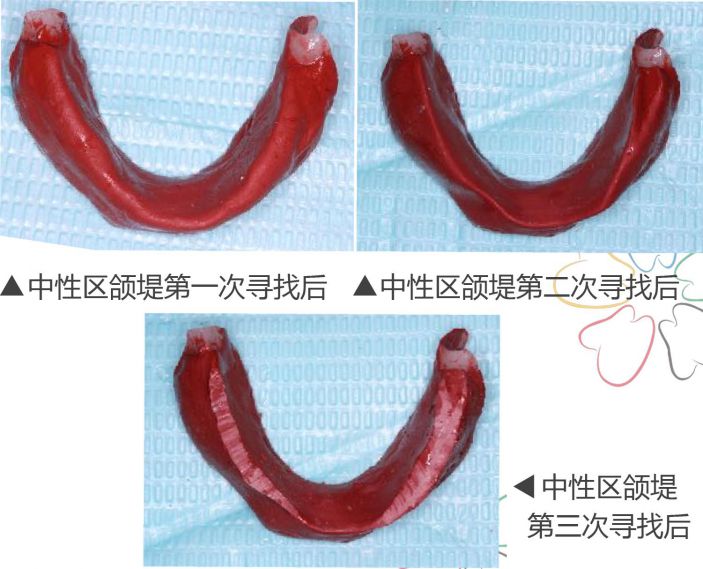

三、尋找中性區